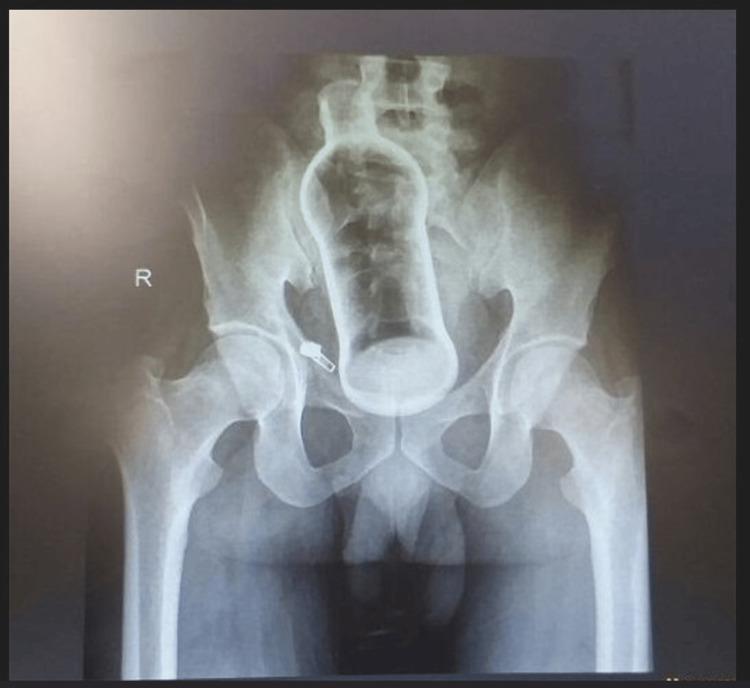

Rectal foreign bodies (RFBs) are foreign bodies in the rectum that pose a challenge to the surgeons in the emergency department. We report a case of an RFB; the patient was a 30-year-old man who put a glass bottle into his rectum on his own. The 10-cm bottle was successfully retrieved through the transanal approach without complication. The patient had no sign of injury or bleeding after the procedure. The patient was stable and was discharged with counseling to avoid such conduct. An effective approach for extraction is to have a structured protocol encompassing prompt diagnosis, extraction techniques, and post-removal assessment. In addition, there is a psychological aspect to RFBs that requires counseling and patient education.

直肠异物是指存在于直肠内的异物,这给急诊科的外科医生带来了挑战。我们报告一例直肠异物病例;患者为一名30岁男性,自行将一个玻璃瓶塞入直肠。这个10厘米长的瓶子通过经肛门途径成功取出,无并发症发生。术后患者没有受伤或出血迹象。患者情况稳定,经劝告避免此类行为后出院。有效的取出方法是制定一个结构化方案,包括快速诊断、取出技术和取出后评估。此外,直肠异物还涉及心理方面,需要进行咨询和患者教育。